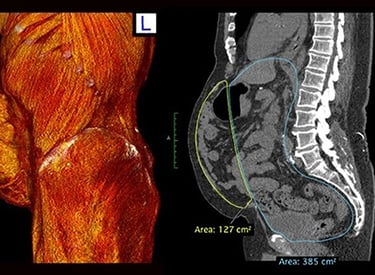

Loss of abdominal domain

Patients with complex hernias, a history of failed hernia repairs, or abdominal trauma may require abdominal wall reconstruction. Large hernias can cause abdominal deformities, discomfort, and a significant impact on quality of life. These hernias do not resolve without surgical intervention.

The Procedure